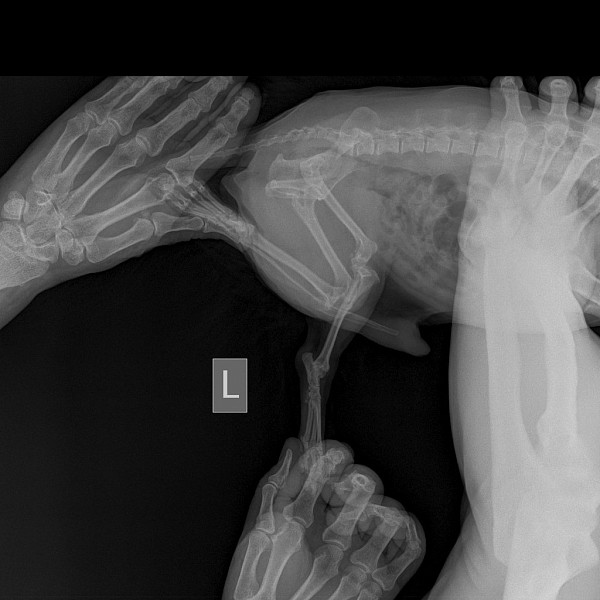

Рентген Задней Лапы Кошки: Нормы и Диагностика